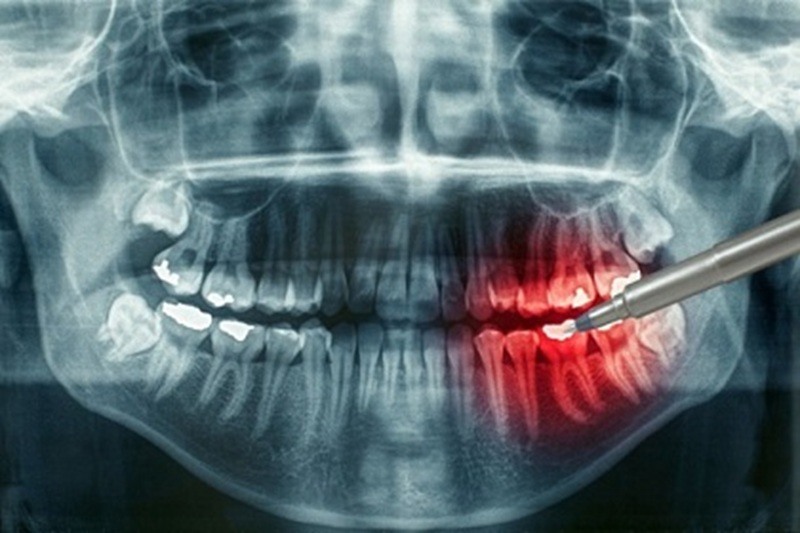

Быстрое определение зубной проблемы через моментально подготовленный снимок с минимальным вредом для здоровья пациента. Радиовизиография является современным и результативным исследованием причин боли зуба. Высококачественное фото зуба с применением контрастных цветов способствует быстрому принятию решения в лечении сразу после радиовизиографии.

Снимок проводится в стоматологическом кабинете, при помощи направленного рентгена к больному зубу. Пациенту предлагают расположиться в стоматологическом кресле. Для меньшего контакта рентгена с областью облучения, на зуб устанавливают небольшой датчик, благодаря которому выводится на монитор общая картина патологии канала. Единственным усилием пациента во время процедуры можно назвать секундное удержание датчика.

Безопасное проведение радиовизиографии цифровым аппаратом проходит у лечащего стоматолога, без перехода в специализированные кабинет. Визиография может быть использована в момент самого лечения или до и после его проведения, на усмотрение доктора. Рентген аппарат считывает полость рта и каналы на матрицу и в дальнейшем выводит контрастное изображение на экран или бумагу. Процедура займет несколько секунд.